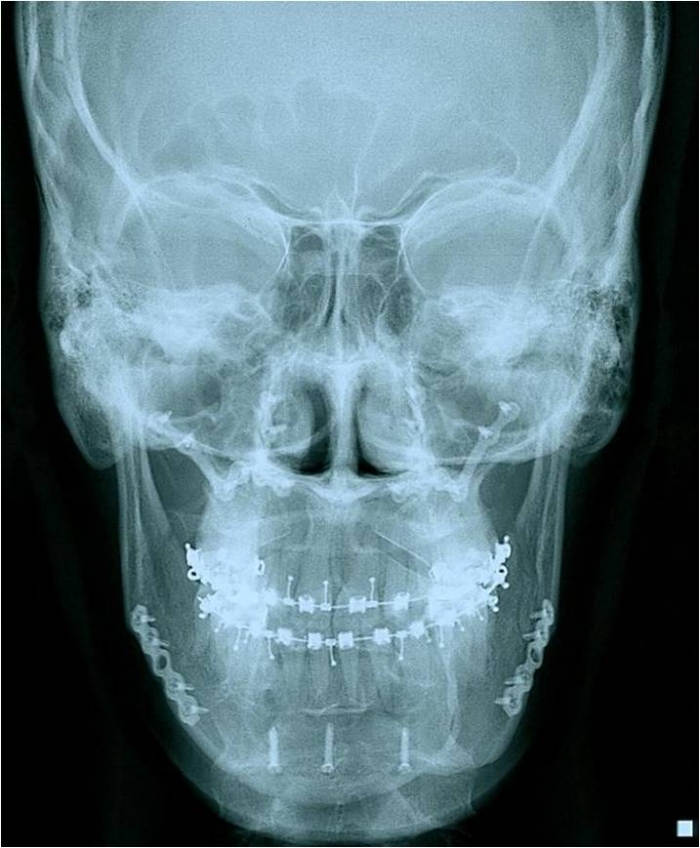

Telerradiografia frontal após a cirurgia - Clínica Cliniface

Telerradiografia frontal após a cirurgia